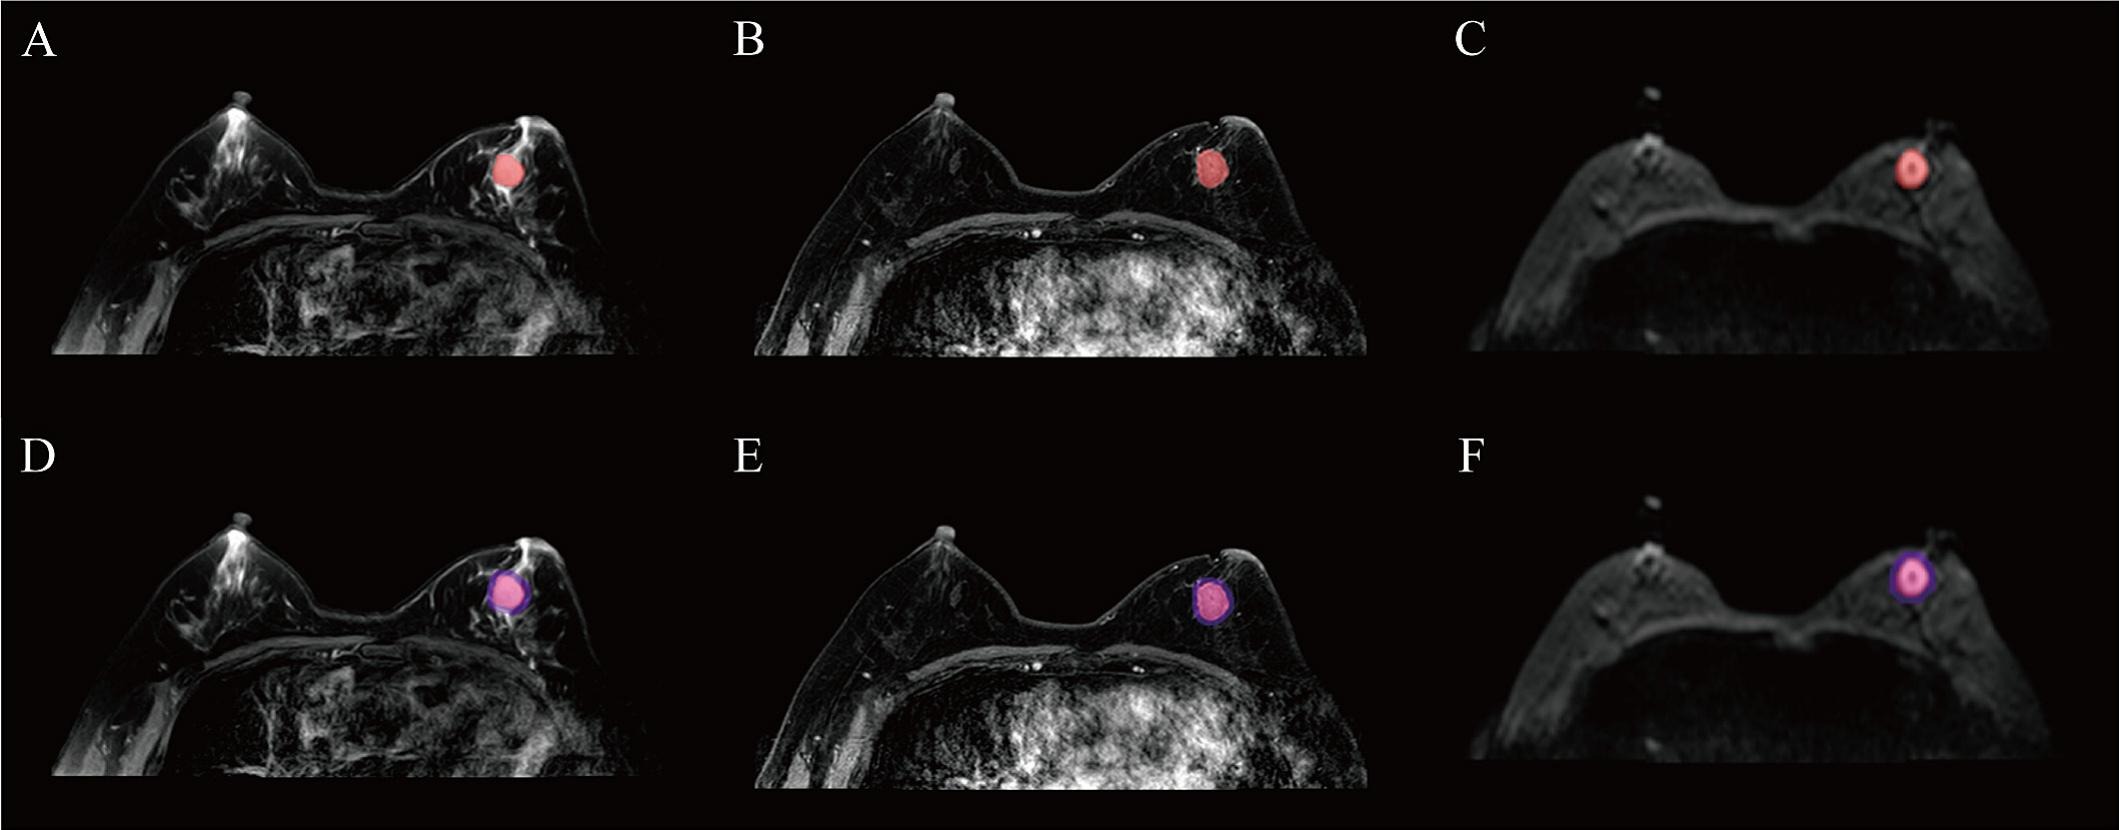

Images depict axial MRI scans in a 50-year-old premenopausal female patient with biopsy-proven 12-mm invasive lobular cancer in the lower outer quadrant of the left breast. Upper images are subtracted dynamic contrast-enhanced (DCE) MRI scans from the first and second postcontrast acquisitions. Lower images are ultrafast MRI scans obtained within 24 hours after the DCE study (four consecutive subtracted dynamic frames from time points [T] 6–9). There is marked background parenchymal enhancement (BPE) on the DCE MRI scans. Thus, the known cancer (arrow) is barely visible; it exhibits only slightly stronger enhancement than the normal fibroglandular tissue, which results in low conspicuity. At ultrafast MRI there is less BPE, and still the cancer is barely visible because it starts to enhance simultaneously with the BPE. The conspicuity of the cancer is even reduced compared with the DCE series. Both of the readers missed this cancer on both the DCE and ultrafast MRI scans. RSNA